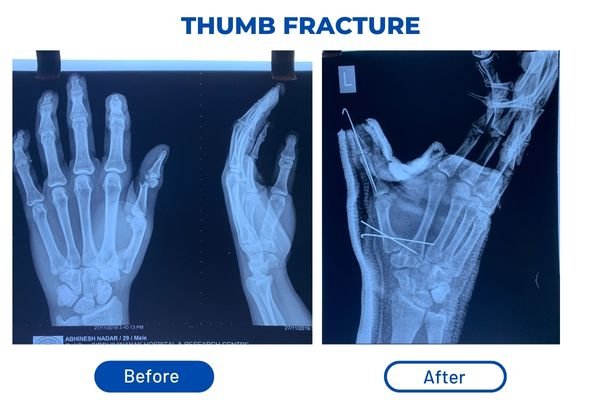

Fracture Treatment Surgery